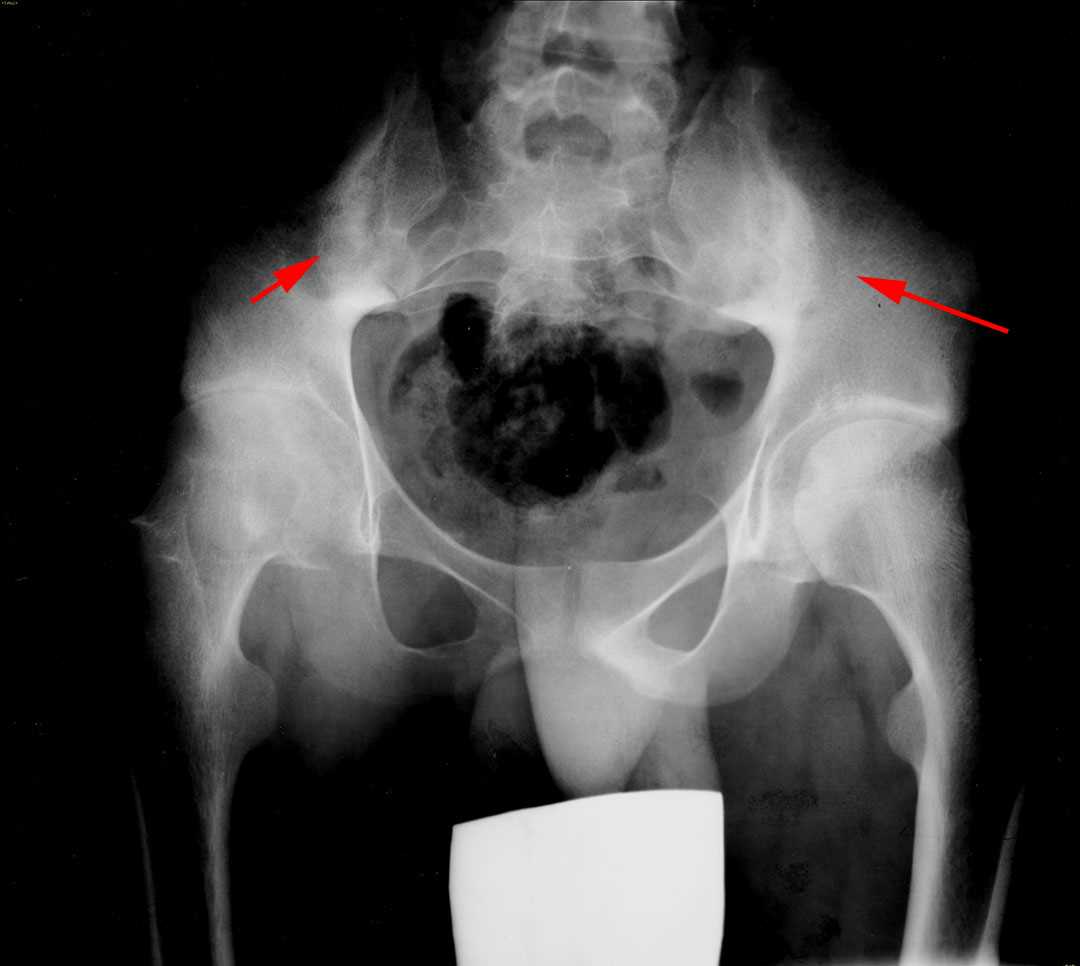

Ankylosing Spondylitis X Ray Si Joint . Dosing informationwatch videos for hcps Ankylosing spondylitis (as) is a chronic, inflammatory disease primarily affecting the axial spine that can manifest with a range of clinical signs and symptoms. Ankylosing spondylitis is a chronic seronegative autoimmune spondyloarthropathy characterized by bridging spinal osteophyte formation, enthesitis, sacroiliitis,. Ankylosing spondylitis is a type of arthritis that causes pain and stiffness in your spine and other joints. Ankylosing spondylitis most commonly affects the sacroiliac joints first. Ankylosing spondylitis often affects the sacroiliac or si joint, which may cause pain in the lower back or buttocks. Typical appearance of bamboo spine with multiple syndesmophytes between the vertebral bodies are seen. Imaging is an integral part of the management of patients with ankylosing spondylitis and axial spondyloarthritis. Early changes of sacroiliitis (inflammation of the sacroiliac joints) are not. It typically affects your sacroiliac joint, where your spine and pelvis meet.

Ankylosing Spondylitis with SI Joint Fusion Musculoskeletal Case Ankylosing Spondylitis X Ray Si Joint Imaging is an integral part of the management of patients with ankylosing spondylitis and axial spondyloarthritis. Ankylosing spondylitis is a type of arthritis that causes pain and stiffness in your spine and other joints. Dosing informationwatch videos for hcps Ankylosing spondylitis most commonly affects the sacroiliac joints first. Ankylosing spondylitis is a chronic seronegative autoimmune spondyloarthropathy characterized by bridging spinal. Ankylosing Spondylitis X Ray Si Joint.

Ankylosing Spondylitis with Sacroiliac Joint (SI Joint) Fusion Ankylosing Spondylitis X Ray Si Joint It typically affects your sacroiliac joint, where your spine and pelvis meet. Ankylosing spondylitis (as) is a chronic, inflammatory disease primarily affecting the axial spine that can manifest with a range of clinical signs and symptoms. Typical appearance of bamboo spine with multiple syndesmophytes between the vertebral bodies are seen. Ankylosing spondylitis is a chronic seronegative autoimmune spondyloarthropathy characterized by. Ankylosing Spondylitis X Ray Si Joint.

Ankylosing Spondylitis with Sacroiliac Joint (SI Joint) Fusion Ankylosing Spondylitis X Ray Si Joint Ankylosing spondylitis often affects the sacroiliac or si joint, which may cause pain in the lower back or buttocks. Early changes of sacroiliitis (inflammation of the sacroiliac joints) are not. Ankylosing spondylitis is a type of arthritis that causes pain and stiffness in your spine and other joints. Ankylosing spondylitis most commonly affects the sacroiliac joints first. Dosing informationwatch videos. Ankylosing Spondylitis X Ray Si Joint.